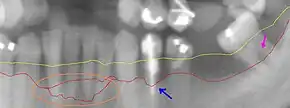

Subgingival biofilm

Subgingival biofilm is plaque that is located under the gums. It occurs after the formation of the supragingival biofilm by a downward growth of the bacteria from above the gums to below. This plaque is mostly made up of anaerobic bacteria, meaning that these bacteria will only survive if there is no oxygen. As this plaque attaches in a pocket under the gums, they are not exposed to oxygen in the mouth and will therefore thrive if not removed.[10]